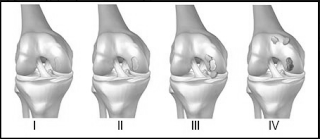

Хондромаляция 2 3 степень

Хондромаляция 2 3 степень 88 фото